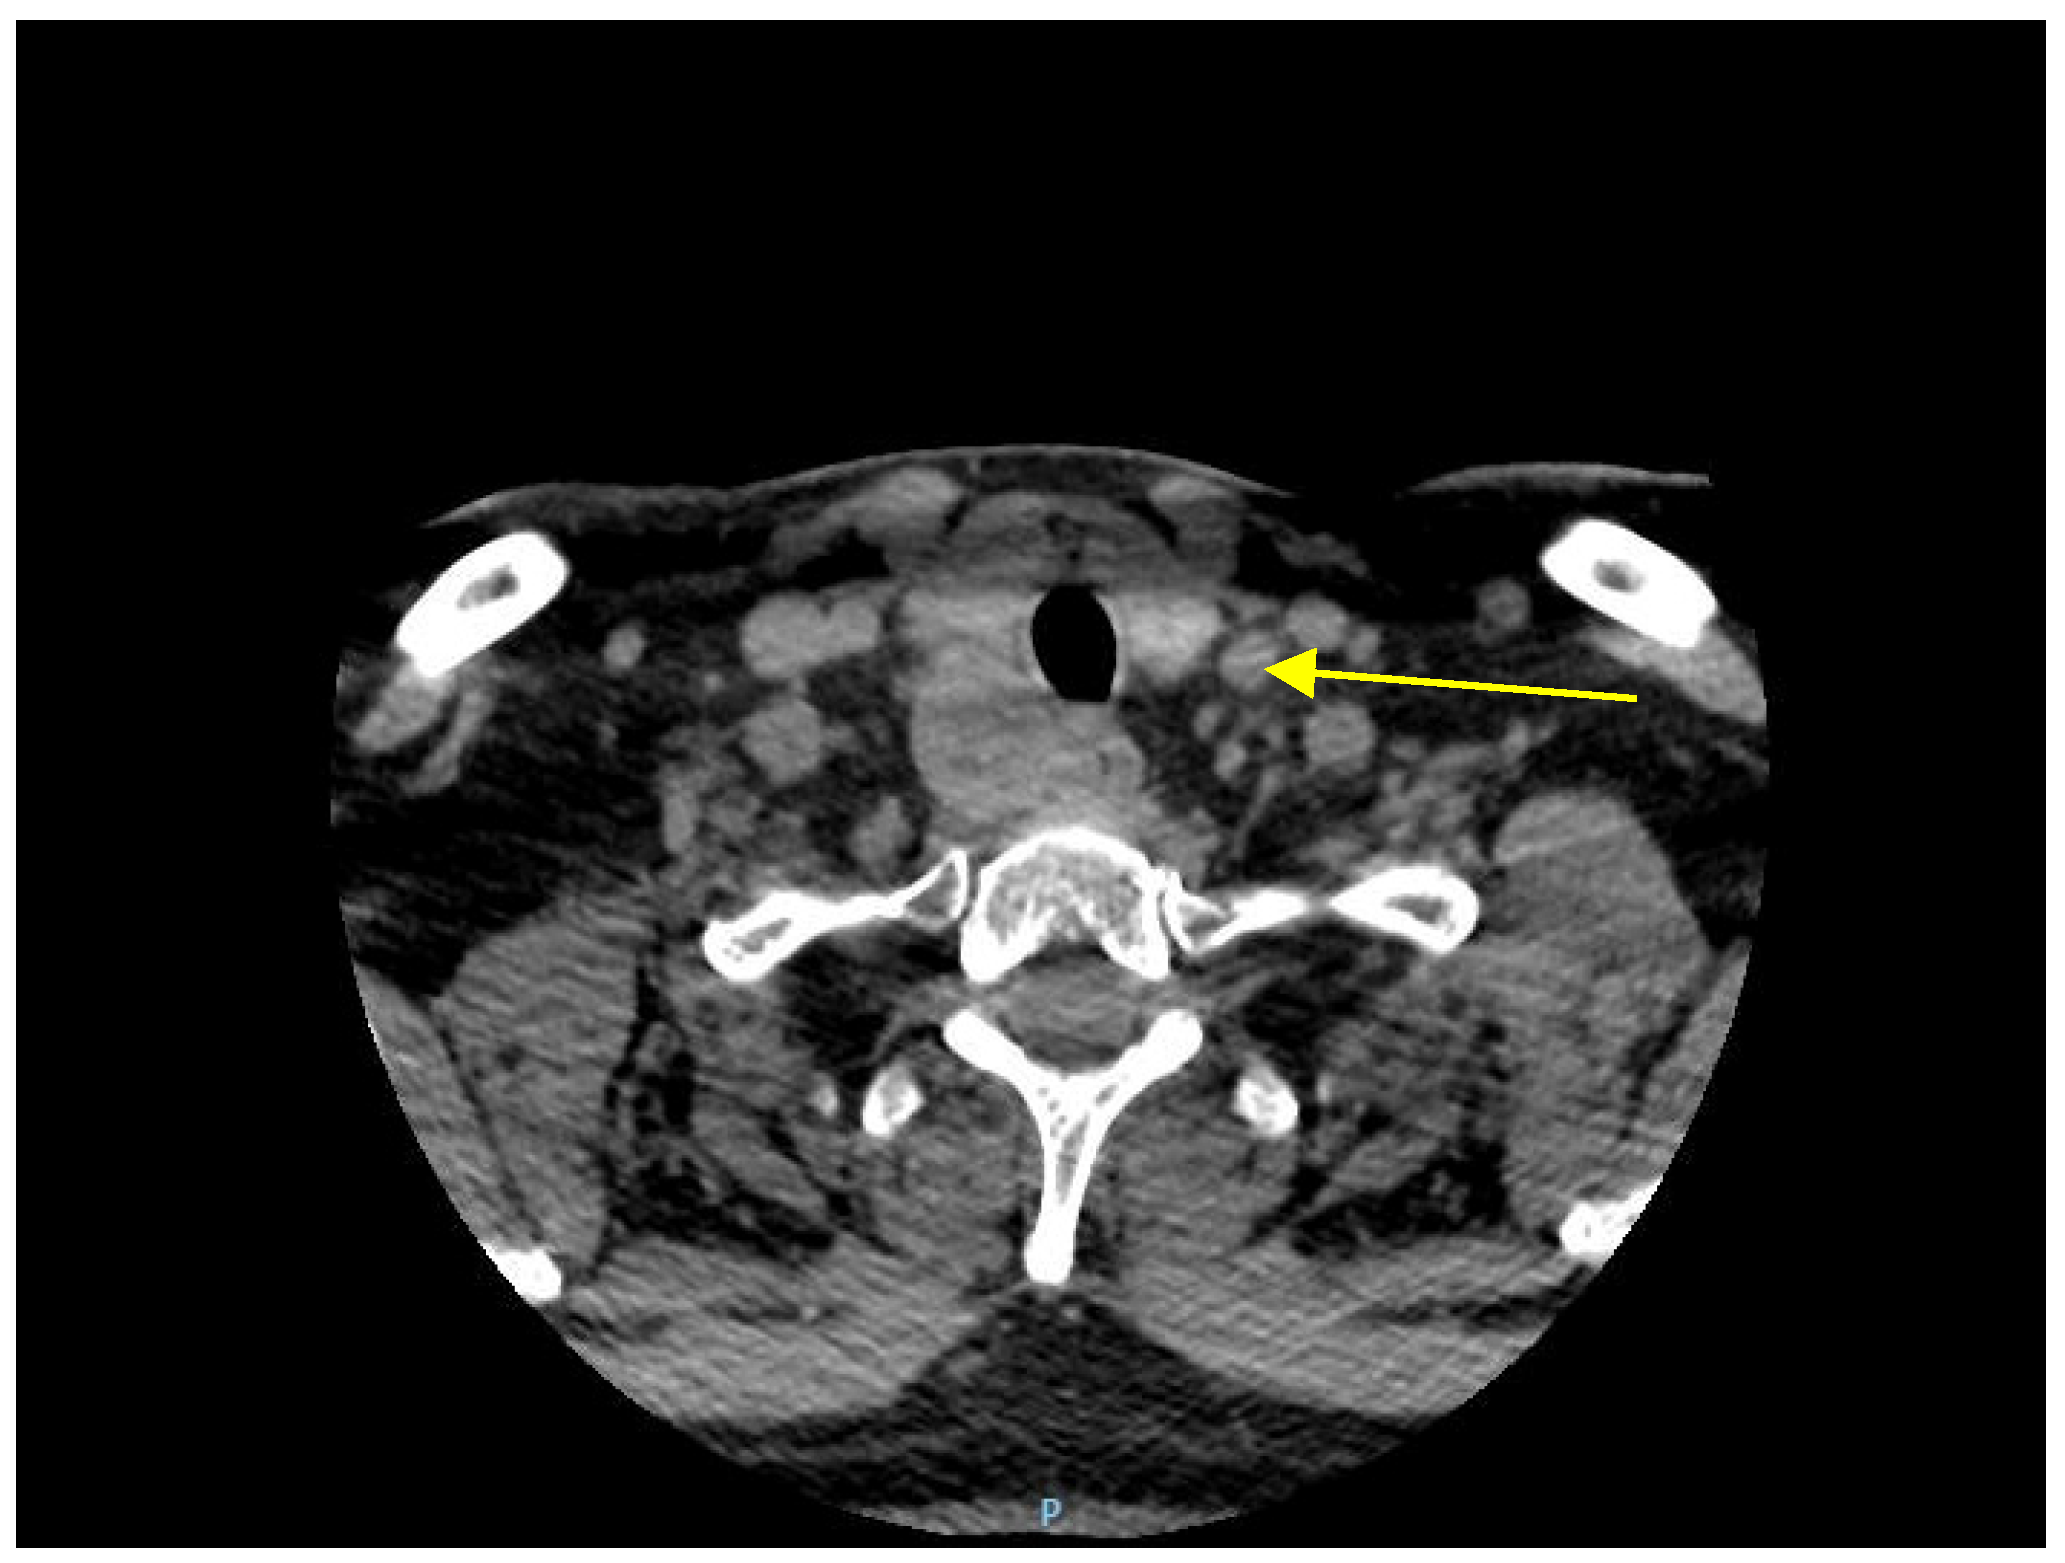

Ultrasonography examination of the cervical area revealed an enlarged, irregular, low-echo, and non-vascularized right inferior parathyroid gland. A distinct mass was detected in the right cervical region, displaying well-defined borders, heterogeneous echogenicity, predominantly low echoes, microcalcifications and fibrotic areas, and increased vascularity on Doppler imaging. The dimensions of the mass were measured at 3.7 cm × 5.0 cm × 2.8 cm, and it was not possible to definitively exclude the possibility of a parathyroid adenoma. Subsequently, a neck CT scan confirmed the presence of a nodular mass within the right inferior parathyroid gland (Figure 1).

Figure 1.

A cervical CT scan shows a 5 cm nodular mass in the right inferior parathyroid gland.